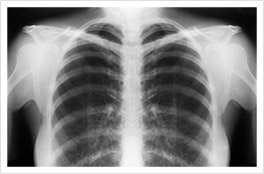

Mesothelioma X-Ray Scans

X-rays are mesothelioma imaging scans that offer a fast, low-dose way to look for problems in the chest. Doctors use them to spot fluid around the lungs, areas of unusual thickening or a collapsed lung that may signal pleural disease.

Doctors check for warning signs linked to mesothelioma, like pleural effusion, pleural thickening, or a partly collapsed lung. X-rays can miss small or early tumors, and they do not diagnose cancer alone. If your X-ray raises concern, your doctor will order advanced scans and, if needed, a biopsy to be sure.

What Does Mesothelioma Look Like on an X-Ray?

On a chest X-ray, pleural or pericardial mesothelioma tumors appear as wispy white areas around the lungs, while calcified tumors appear bright white. Bones appear white and healthy lungs are dark. Most abnormalities appear as lighter areas that are hazy or solid.

Tumors and scarring may distort chest anatomy. Compressed lungs or a raised diaphragm can be visible on an X-ray.

X-rays are 2D, making it hard to determine if a tumor is in the lung, pleura or the mediastinum around the heart. Additionally, X-rays don’t clearly show peritoneal or testicular mesothelioma. CT, MRI and PET/CT scans offer more detailed images for all mesothelioma types.